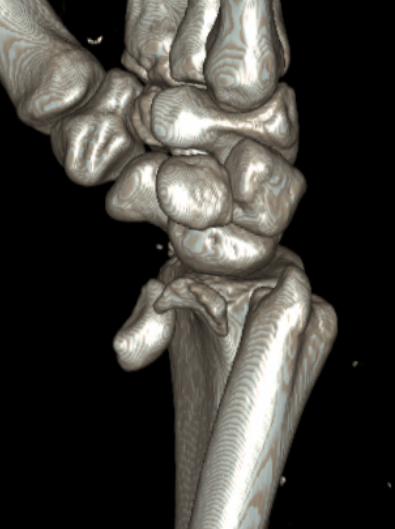

CT

Trans-scaphoid perilunate dislocation

Perilunate dislocation